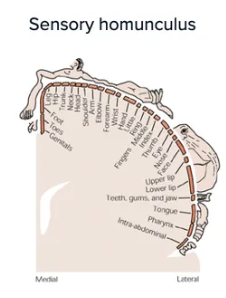

spatial arrangement and density of sensory receptors is mapped onto ___

the primary sensory cortex

76

New cards

spatial arrangement and density of sensory receptors reflects

degree of sensory sensitivity

77

primary motor cortex

motor maps reflect density of neuronal innervation, correlated with degree of fine motor control

<p>motor maps reflect density of neuronal innervation, correlated with degree of fine motor control</p>

78

primary somatosensory cortex

abundance of neurons receiving input from specific region is associated with degree of sensory sensitivity

<p>abundance of neurons receiving input from specific region is associated with degree of sensory sensitivity</p>

79

more sensitive the area → (more/less) sensory receptors/neurons needed to innervate it

MORE